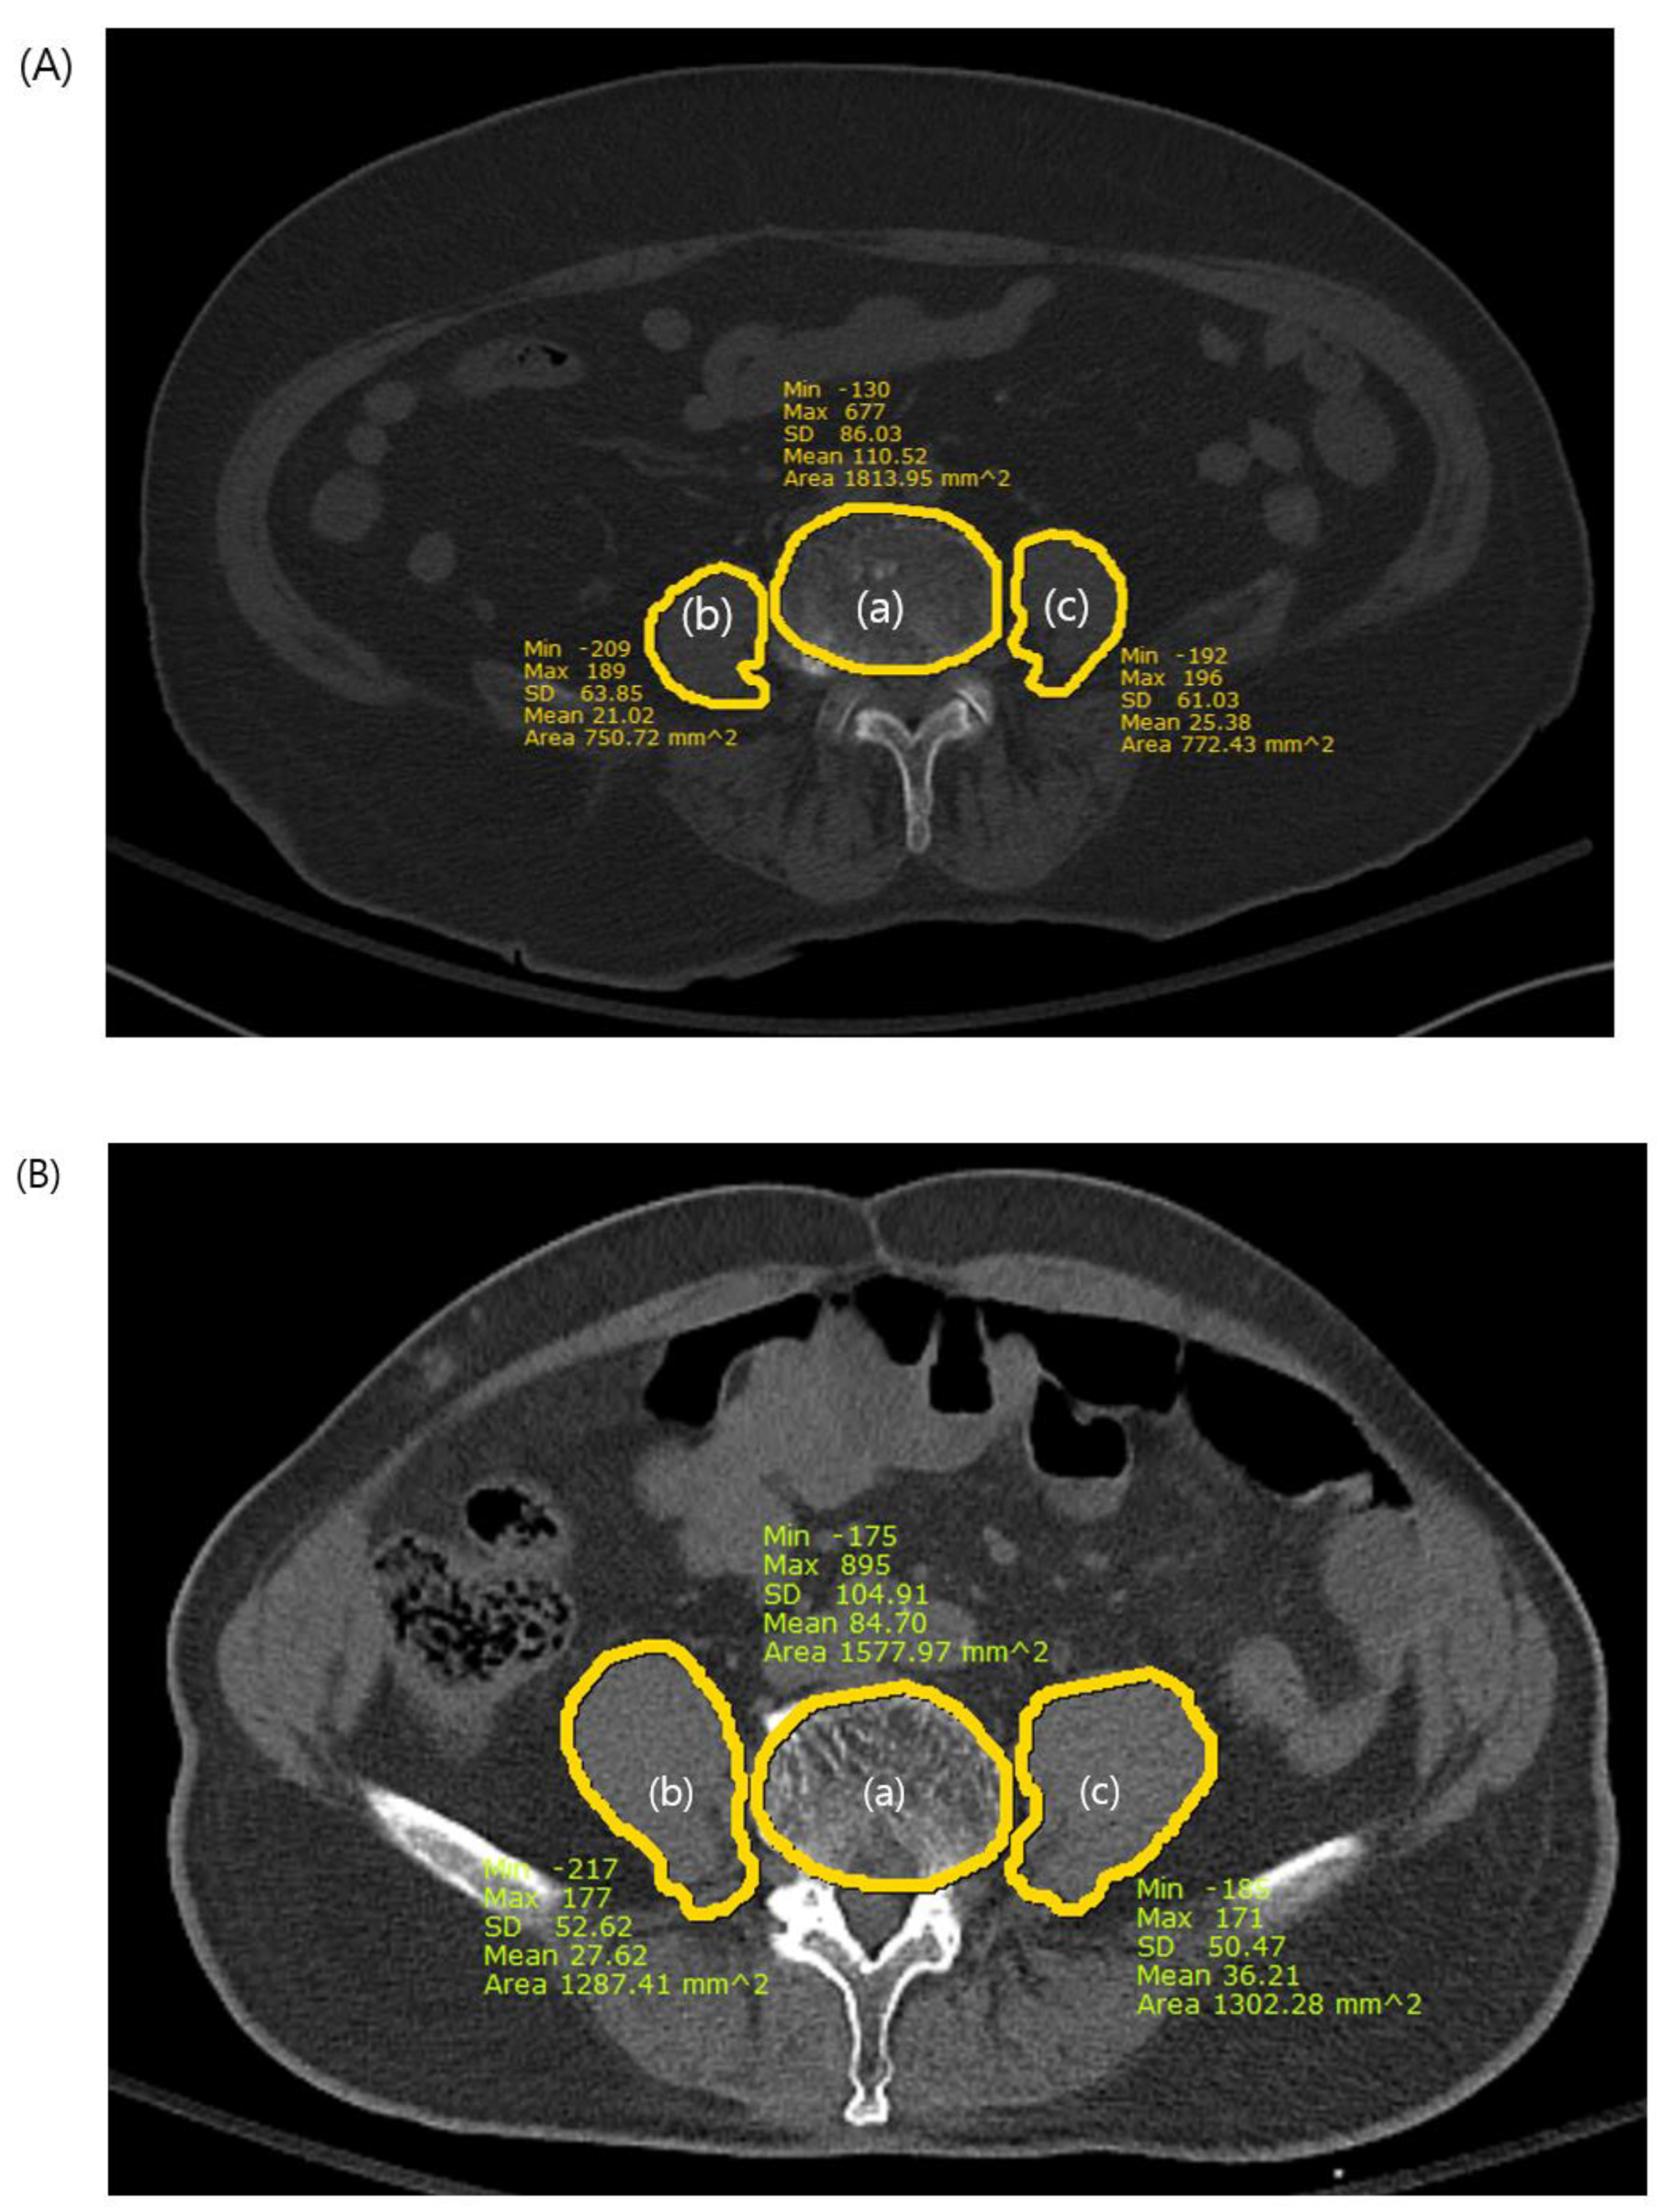

We measured the psoas-lumbar vertebral index (PLVI) to evaluate central sarcopenia from axial sections of preoperative CT images using measurements from the picture archiving and communication system (PACS). The PLVI was established following the criteria established in previous studies [11,12,13] and was calculated as the ratio of the average of the areas of both the right and left psoas muscles at the level of the inferior endplate of the fourth lumbar vertebra to the area of the fourth lumbar vertebra (Figure 2). Sarcopenia was defined as a PLVI within the lowest 25% for each sex [7,9,10], and patients were categorized into sarcopenic and nonsarcopenic groups for analysis.

Figure 2. The psoas-lumbar vertebral index (PLVI) measurement. (a) L4 vertebral body area, (b) right psoas area, (c) left psoas area. PLVI = [(b + c)/2]/a (A): PLVI of the sarcopenic patient on computed tomography. The PLVI= 0.41. (B): PLVI of the nonsarcopenic patient on computed tomography. The PLVI = 0.84.